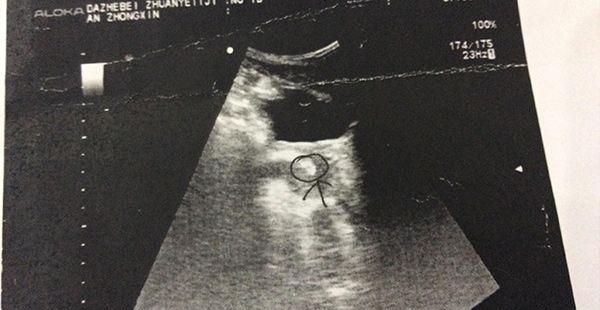

B超是一项通过超声波传递途经的一项检查,是一种非手术的诊断性检查,在临床上多有运用,可以让患者在无痛、无损伤的情况下放心接受检查。虽说这项检查很方便,但对于一些人而言,也是头一次做,那么接下来本文就向大家介绍相关的流程攻略。

B超是一种超声波检查